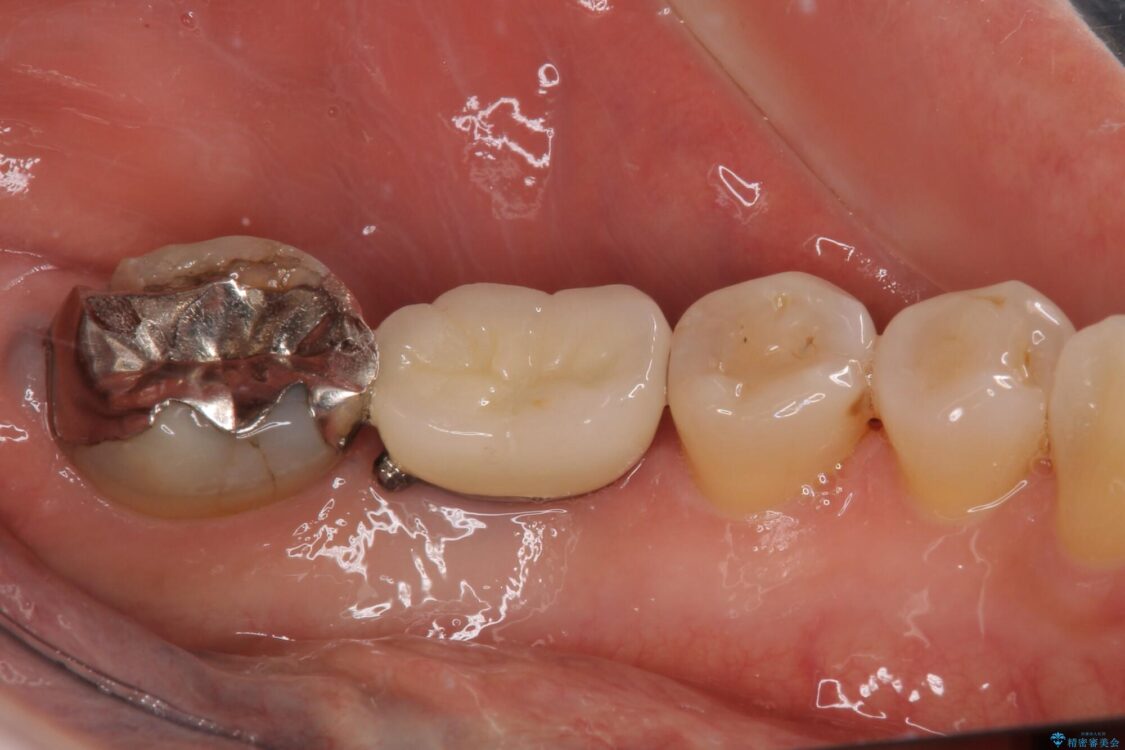

銀歯の装着されている奥歯がしみるとのことで来院された患者様です。

銀歯周辺の歯が欠けており、むし歯も進行している状態であったので、オールセラミッククラウンにて補綴治療を行うこととしました。

• しみる奥歯 オールセラミッククラウンによる補綴治療 治療前画像